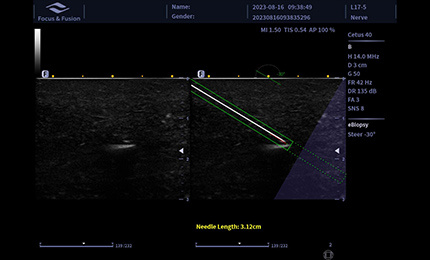

eBiopsy+

Obraz igły punkcyjnej jest wzmocniony przez odchylenie wiązki akustycznej, obejmujące wzmocnienie igły, renderowanie czerwonego końca igły, wirtualny przebieg igły oraz linię skali, wspierające automatyczne sterowanie.